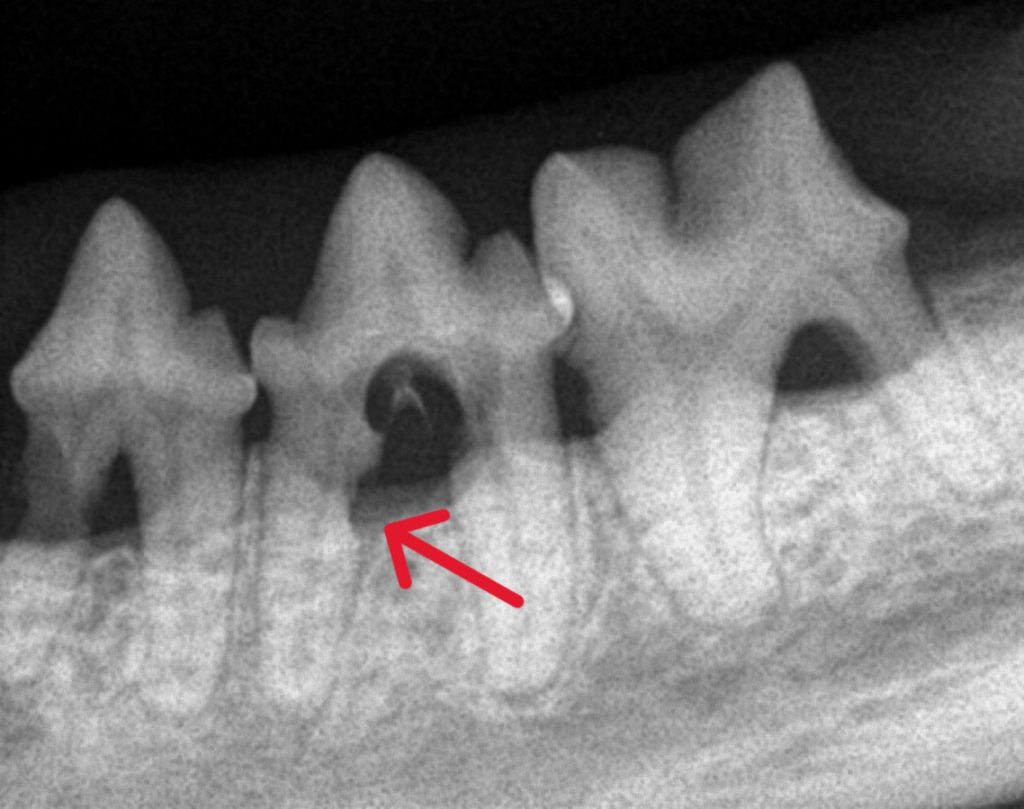

見た目では歯がしっかりしているように見えても、歯科用レントゲンを撮ると歯が根元から溶けていることがはっきり分かります。

吸収病巣(FORL:Feline Odontoclastic Resorptive Lesions)は、歯の表面や根の部分が少しずつ溶けていってしまう病気です。

当院では、歯科用レントゲンで状態を確認し、必要に応じて部分的あるいは全体的に抜歯を行います。

外からは分かりにくいため、レントゲン検査で初めて診断できるケースが多いのが特徴です。